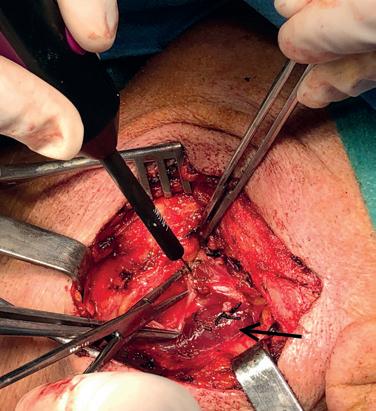

peripheral arterial disease (PAD) to receive either infrainguinal bypass or endovascular intervention. The trial consisted of two parallel trials: Cohort 1 included patients with single-segment GSV; Cohort 2 included patients who lacked single-segment GSV and therefore alternative autogenous vein or prosthetic was used in those randomized to the open arm.

According to Farber, the best way to evaluate whether a patient has single-segment GSV—one he says needs to be at least 2.5mm in diameter, but ideally above 3mm, and must be free of thrombus—is by using duplex ultrasound. Speaking to Vascular Specialist on this topic, Menard notes that while assessment of the vein is common practice for vascular surgeons, it is not for other specialties. In the wake of BEST-CLI, he suggests that evaluation of the GSV—a “very important” part of the assessment for treatment—should be included in the guidelines.

The investigators found that surgery was more effective than endovascular therapy in the Cohort 1 patients. At AHA, Farber revealed that there was a reduced rate of major adverse limb event (MALE) or all-cause death—the primary endpoint—in patients with good single-segment GSV who underwent open surgery, as well as fewer major reinterventions, at median follow-up of 2.7 years. The maximum follow-up time in these patients was seven years.

Going into the details, Farber noted that Cohort 1 included 1,434 patients with single-segment GSV who were randomized 1:1 to either surgical or endovascular treatment. At median follow-up, the rate of MALE or all-cause death was 42.6% in the surgery arm compared to 57.4% in the endovascular arm (hazard ratio [HR], 0.68; 95% confidence interval [CI], 0.59–0.79; p<0.001). In terms of secondary endpoints, he revealed that 10.4% of patients in the surgery arm underwent above-ankle amputation of the index limb versus 14.9% in the endovascular arm, in addition to rates of 9.2% vs. 23.5% for major reintervention on the index limb, and 33% vs. 37.6% for all-cause death for patients in the open and endovascular arms, respectively. In patients who did not have adequate saphenous vein, i.e. those in Cohort 2, there were no significant differences in the primary endpoint. Farber detailed that this group included 396 patients who were randomized 1:1 to either surgical or endovascular treat-